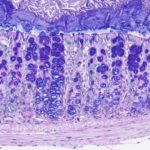

Immagine, Tbx3 (verde) svolge un ruolo cruciale per la funzione e il mantenimento dei sazietà dei neuroni nel cervello. Credito: modificato da Quarta, C.

“Nel nostro recente studio abbiamo scoperto che un fattore di trascrizione chiamato Tbx3 svolge un ruolo chiave in questo meccanismo“, afferma Carmelo Quarta, descrivendo le nuove scoperte. “In particolare, in assenza di Tbx3, i neuroni responsabili della produzione di un senso di sazietà non sono più in grado di sintetizzare i messaggeri molecolari attesi“. Applicando una vasta gamma di tecniche, gli scienziati sono stati quindi in grado di dimostrare che Tbx3 svolge un ruolo fondamentale nel mantenimento del metabolismo energetico e dello zucchero.

“Sia in un modello preclinico che in moscerini della frutta, l’assenza di Tbx3 porta a una sorta di crisi di identità dei neuroni della sazietà, con conseguente obesità“, afferma Alexandre Fisette. Gli stessi percorsi di segnalazione sembrano essere presenti anche negli umani: “In esperimenti preliminari con neuroni umani, siamo stati in grado di dimostrare che i neuroni non sono più in grado di svolgere la loro funzione in assenza di Tbx3”, aggiunge Carmelo Quarta.